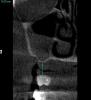

SergeyAL Опубликовано 29 мая, 2013 Поделиться Опубликовано 29 мая, 2013 коллеги столкнулся с такой ситуацией 5 лет назад были установлены поднадкостничные имплантаты имени д-ра Раада пациенту пообещали, что 5 лет они точно прослужат на срезах КТ видно, что прослужили, но в некоторых местах албвеолярного отростка не осталось после их службы)) послу удаления их остались сплошные рубцы, удалять которые смысла не импло, т.к. они были спаяны со Шнайдеровой мембраной или то, что от нее осталось последние фотографии через 4 месяца после их удаления, слизистая представляет собой сплошной рубец. коллеги, поделитесь, какую тактику применяете при выраженных рубцовых деформациях, когда впереди еще костная пластика, имплантация и т.д. Ссылка на комментарий

SergeyAL Опубликовано 30 мая, 2013 Автор Поделиться Опубликовано 30 мая, 2013 коллега, каких синусов, толщина в области синуса менее 3-х мм, а расстояние от костной ткани до предполагаемой реставрации 10-15мм!!!!! Ссылка на комментарий

SergeyAL Опубликовано 30 мая, 2013 Автор Поделиться Опубликовано 30 мая, 2013 там выраженная редукция тканей по ширине,даже в в области синуса около 3 мм Ссылка на комментарий

SergeyAL Опубликовано 30 мая, 2013 Автор Поделиться Опубликовано 30 мая, 2013 там не везде есть костная пластинка, местами рубцы из ротовой полости спаяны со Шнайдеровой мембраной или что там от нее осталось Ссылка на комментарий